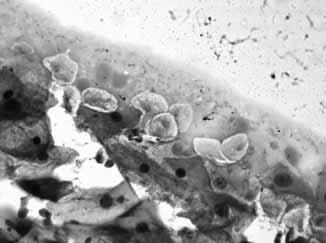

Tsütoloogia valdkonnast on seni ainsana oma uuringu teinud O. Pilitsina (joonis 3). Tema tööd „Emakakaela patoloogiliste muutuste diagnostika õppematerjal“ (2015) hindasime sedavõrd vajalikuks, et praeguseks on koostatud sellele tuginedes, seda parandades ja üht-teist lisades elektrooniline käsiraamat „Emakakaela patoloogiliste muutuste diagnostika“ (Pilitsina jt 2016), mis on kättesaadav kõrgkooli kodulehelt. Ekspertide arvamustest lõputöö kohta ilmnes, et nende seisukohalt võiks olla veelgi enam fotosid, näiteks perinukleaarsest halost ja silinderepiteeli erinevatest rakkudest, aga mainitud ka Bethesda süsteemi. Ettepanekuid arvestati nii palju kui võimalik, sest lõputööl on oma mahupiirangud, mida töö vormistamisel tuleb silmas pidada. Samas oli meil hiljem elektroonilist käsiraamatut koostades võimalik pakutud materjale lisada.

Joonis 3. O. Pilitsina fotod lõputööst. Vasakpoolsel fotol on peale lameepiteeli rakkude näha mitmeid Trichomonas vaginalis’e heledaid rakke ja parempoolsel lisaks suurele lameepiteeli rakule ka Candida spp. mütseeli niiti